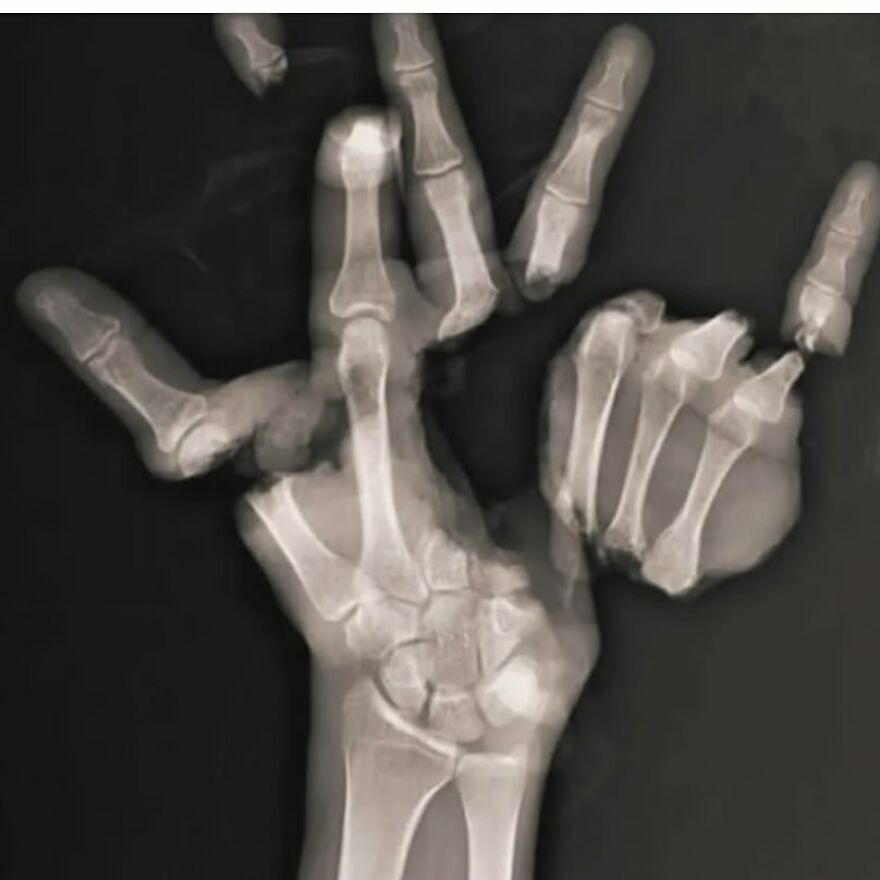

Plain radiograph of wrist joint shows polydactyly with duplication of ulna, duplication of ulnar side of carpal bones, metacarpals and phalanges, absence of radius and absence of thumb. Eight triphalangeal digits are seen. The middle phalanx of medial index finger is hypoplastic